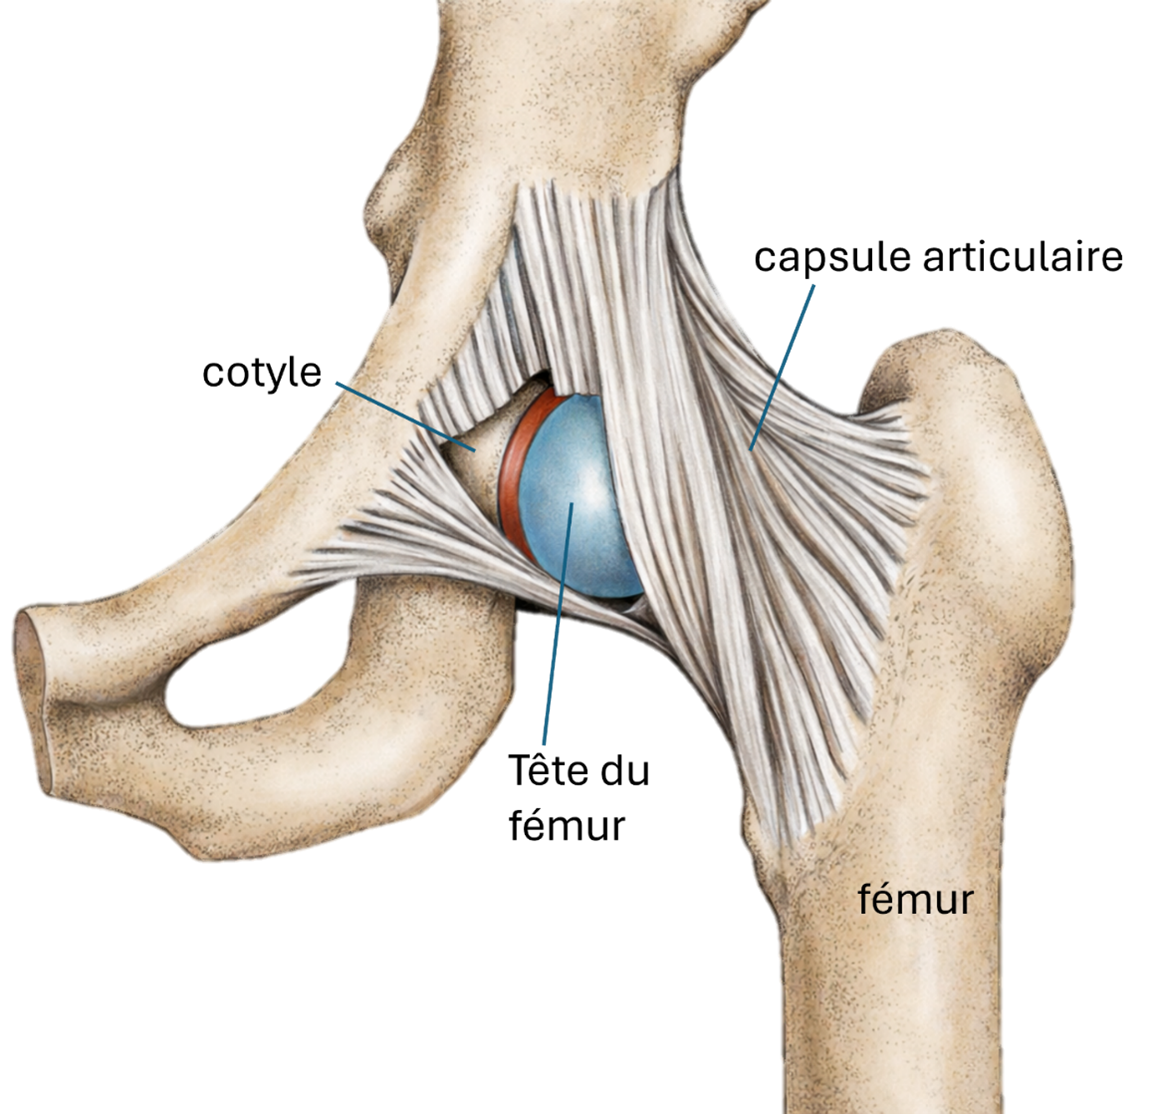

Qu’est-ce que la hanche ?

La hanche est une articulation entre la tête du fémur et le cotyle (partie du bassin).

Elle est conçue pour permettre des mouvements amples et fluides, tout en supportant des charges importantes (marche, escaliers, activités).